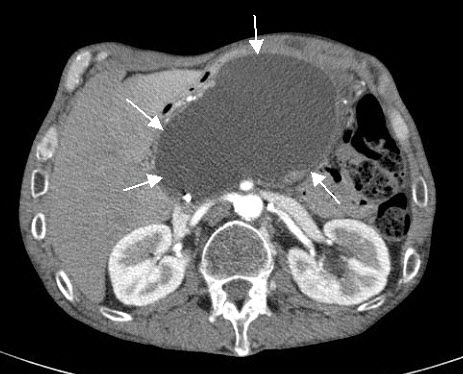

Η αξονική τομογραφία αποτελεί τη μέθοδο εκλογής για την εξέταση του παγκρέατος, γιατί υπερέχει στην απεικόνιση της ανατομικής δομής του οργάνου και των γύρω απ’ αυτό ιστών. Ωστόσο, δεν παρέχει περισσότερες πληροφορίες από το υπερηχογράφημα αναφορικά με τη λιθίαση των χοληφόρων. Η δυναμική αξονική τομογραφία, που πραγματοποιείται με την ταυτόχρονη ενδοαγγειακή έγχυση σκιαγόνου ουσίας, είναι η μόνη απεικονιστική εξέταση με την οποία αποτιμάται αξιόπιστα η βαρύτητα της οξείας παγκρεατίτιδας. Με αυτήν απεικονίζονται οι ενδεχόμενες επιπλοκές της οξείας παγκρεατίτιδας, όπως οι νεκρώσεις, το απόστημα, η ψευδοκύστη και αποφασίζεται η ανάγκη για πρώιμη χειρουργική επέμβαση με αντικειμενικά πλέον κριτήρια. Πραγματοποιείται κατά την εισαγωγή του ασθενούς για την επιβεβαίωση της διάγνωσης και μετά από δύο εβδομάδες για τον έλεγχο ανάπτυξης ενδεχομένων επιπλοκών (π.χ. νέκρωση, απόστημα, ψευδοκύστη). Η διαγνωστική ευαισθησία της αξονικής τομογραφίας στην οξεία παγκρεατίτιδα φθάνει το 92%, ενώ η ειδικότητα προσεγγίζει το 100% των ασθενών.

Είναι εμφανές ότι ο καλύτερος και ακριβέστερος τρόπος εκτιμήσεως της βαρύτητας της οξείας παγκρεατίτιδας είναι η αξιολόγηση της παθολογοανατομικής καταστάσεως του παγκρέατος και των γύρω ιστών. Αυτό που πριν από λίγα χρόνια ήταν εφικτό μόνο διεγχειρητικά ή / και νεκροτομικά, σήμερα με τις νέες απεικονιστικές μεθόδους είναι δυνατό να γίνει εύκολα, αναίμακτα και με μεγάλη ακρίβεια, αλλά και σε τακτά χρονικά διαστήματα, ώστε να έχουμε πλήρη εποπτική εικόνα όχι μόνο της δυναμικής εξελίξεως της οξείας παγκρεατίτιδας αλλά και των ανατομικών επιπλοκών της, όπως είναι: η παγκρεατική νέκρωση, η αποστηματοποίηση, ο σχηματισμός ψευδοκύστεων ή και αιμορραγίας.Την ακριβέστερη εικόνα της καταστάσεως του παγκρέατος και του περιπαγκρεατικού λίπους παρέχει η αξονική τομογραφία, ιδίως όταν συνδυάζεται με ενδοφλέβια έγχυση σκιαστικού κατά τη διάρκεια της εξετάσεως (δυναμική παγκρεατογραφία), οπότε είναι δυνατόν να διακριθούν οι περιοχές που έχουν νεκρωθεί. Με τη μέθοδο αυτή, εκτός από τη σταδιοποίηση της βαρύτητας, αναδεικνύονται και τυχόν ανατομικές επιπλοκές της νόσου, όπως οι παγκρεατικές και περιπαγκρεατικές συλλογές, η διάταση του χοληδόχου πόρου.

Η ταξινόμηση της βαρύτητας της οξείας παγκρεατίτιδας σύμφωνα με τα ευρήματα της αξονικής τομογραφίας έχει 5 διαβαθμίσεις (πίνακας 4). Οι δύο πρώτες διαβαθμίσεις (1 και 2) αφορούν την οιδηματώδη μορφή της οξείας παγκρεατίτιδας, ενώ οι τρεις επόμενες (3, 4 και 5) αφορούν τη νεκρωτικοαιμορραγική μορφή.

Πίνακας 4: Διαβαθμίσεις βαρύτητας οξείας παγκρεατίτιδας σύμφωνα με την αξονική τομογραφία

| 1. Φυσιολογική υφή του παγκρέατος |

| 2. Διόγκωση του παγκρέατος με ανομοιογενές παρέγχυμα και μικρές ενδοπαγκρεατικές συλλογές υγρού |

| 3. Όλα τα ανωτέρω και επιπλέον περιπαγκρεατική αντίδραση και νέκρωση του παγκρεατικού παρεγχύματος μικρότερη από 30% |

| 4. Εκτός από τα ανωτέρω, μικρή μονήρης εξωπαγκρεατική συλλογή και νέκρωση του παγκρέατος κατά 30%-50% |

| 5. Εκτός από τα ανωτέρω, μεγάλη εξωπαγκρεατική συλλογή, παγκρεατικό απόστημα και νέκρωση του παγκρεατικού παρεγχύματος μεγαλύτερη από 50% |